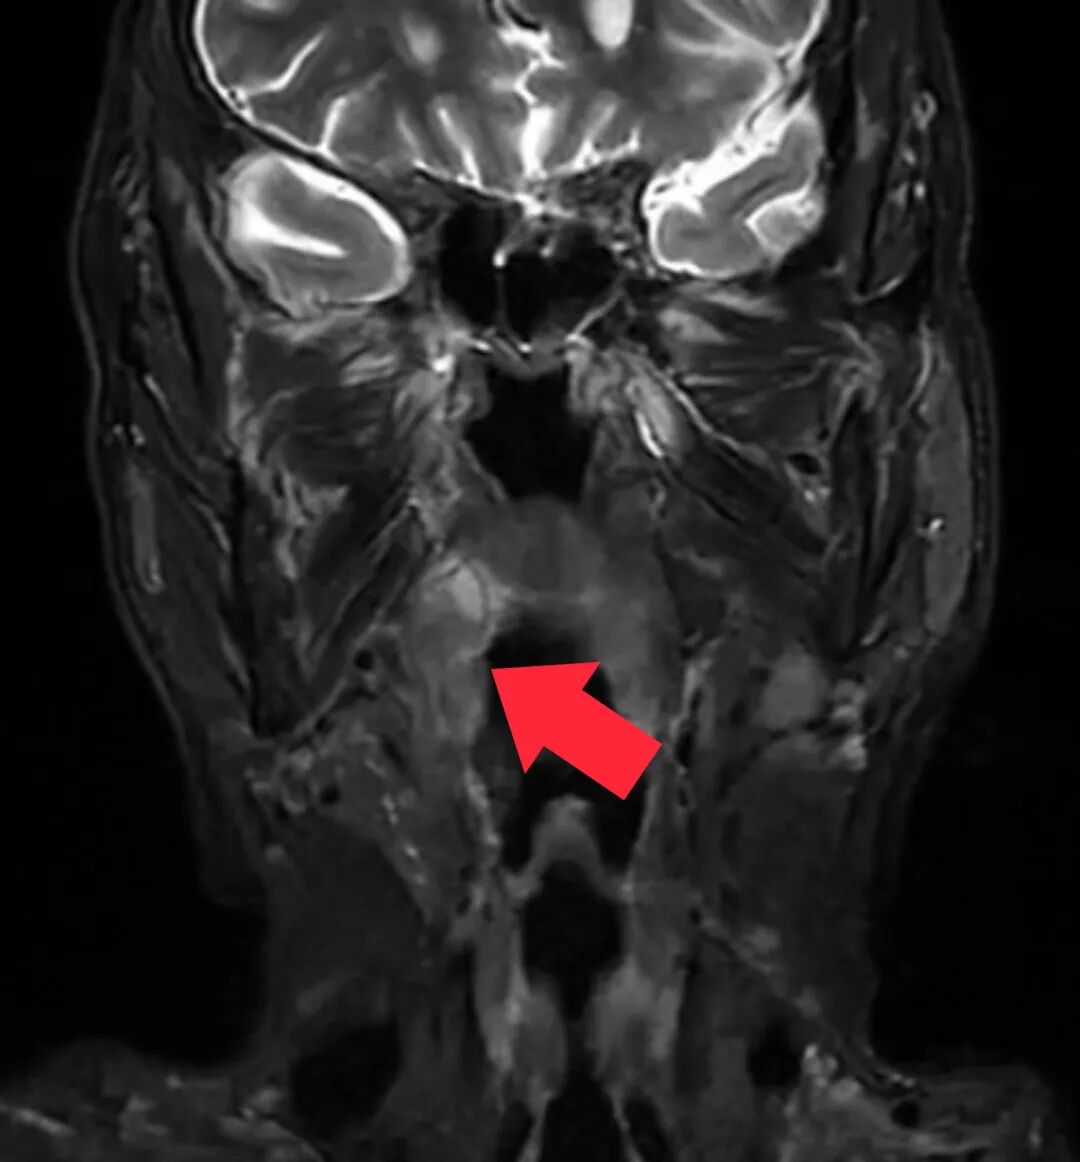

△治疗前

根据叶大叔术前的MRI及喉镜检查,肿瘤分期cT3N2bM0 IVA期 (P16-),结合相关治疗指南,邓泽义主任医师为叶大叔制定了治疗方案:术前新辅助化疗+内镜微创手术+术后放疗。